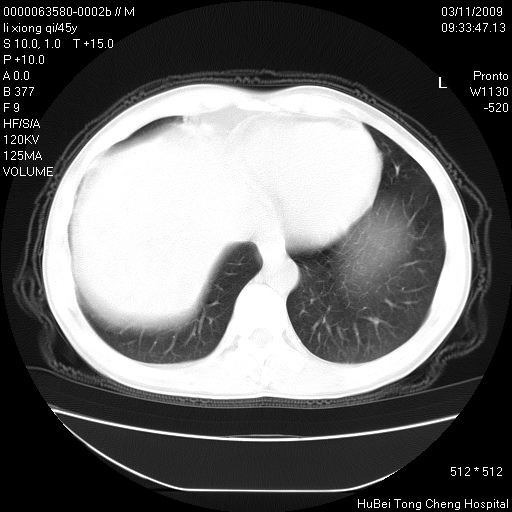

患者 男,45岁。胸痛,咳嗽伴痰中带血1月余。

临床诊断:肺结核?

胸部ct轴位平扫(层厚10mm,螺距1.5,重建间隔10mm),图像如下: